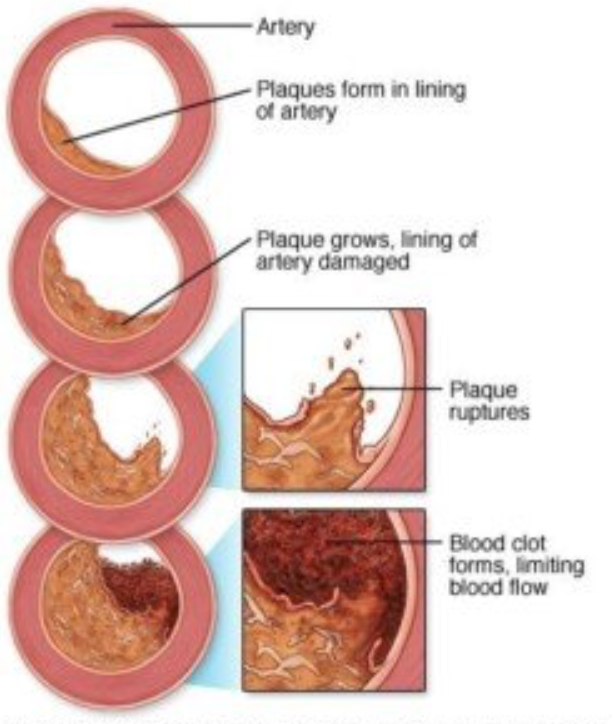

a deposit of plaque within the arterial wall

Atherosclerosis Stages: Healthy Artery, Plaque Formation, and …

Atherosclerosis stages. Normal functions, endothelia disfunction …

Different stages in progression of atherosclerosis [8]. | Download …

Stages of atherosclerosis Stock Vector Image by ©edesignua #144301487